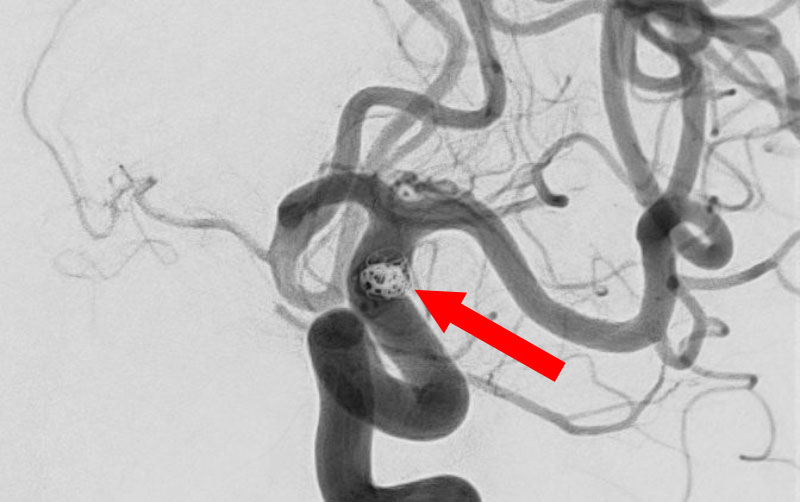

No.1596 手術後